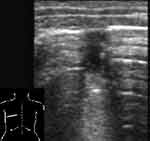

В норме при сканировании датчиком 7,5 МГц последовательно визуализировались следующие структуры: гипоэхогенный слой подкожной жировой клетчатки, тонкая эхогенная полоска наружного листка собственной фасции груди, гипоэхогенные мышечные слои, представленные мышцами плечевого пояса, брюшной стенки и межреберными мышцами с разделяющими их листками фасций. Мышечную ткань нетрудно отличить от жировой клетчатки, даже если полоска фасции отчетливо не видна. Глубже визуализируется эхогенная полоска внутренней грудной фасции, тонкий гипоэхогенный слой рыхлой клетчатки. Затем более тонкая эхогенная полоска, толщиной до 1 мм, являющаяся суммой отражения от париетального, висцерального листков плевры и границы мягкие ткани/воздушная легочная ткань. Просвет между листками плевры не виден. Наружный контур плевры ровный, можно увидеть зазубрину, соответствующую междолевой щели, а внутренняя поверхность эхогенной плевральной полоски не такая четкая и ровная, как наружная. Под ней регистрируются отдельные точечные эхосигналы. При дыхании отчетливо видно скольжение плевральных листков, вместе с висцеральным листком смещаются и точечные эхосигналы. Далее идут постепенно затухающие реверберации отражения от поверхности воздушной легочной ткани (Рис. 1).

[Увеличить]

Рис. 1. Нормальная эхограмма легкого.

Если используется датчик 3,5 МГц можно дифференцировать гипоэхогенную подкожную жировую клетчатку и мышечный слой, затем визуализируется эхогенная полоска плевральных листков и границы воздушной легочной ткани. Ее толщина несколько больше, чем при сканировании датчиком 7,5 МГц и составляет 1-1,5 мм, возможно из-за более глубокого проникновения ультразвуковой волны в воздушную легочную ткань. Во время исследования обращали внимание на положение и подвижность нижних краев легких, их симметричность.